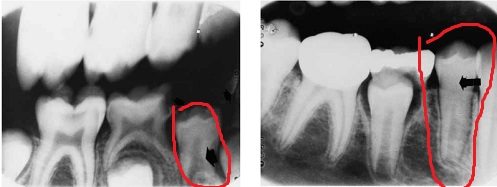

What does an accidental tooth bud removal during primary tooth extraction look like?

The tooth bud may be very small and look similar to an enamel pearl. However, the position of it should be a giveaway.

The tooth bud may also really be more mature and we can consider it an immature tooth. Efrat 2001 shows a case of accidental immature tooth removal during extraction. Tooth #28 was the accidental tooth that was removed. The 2 year follow up looks good other than some coronal pulp calcification.